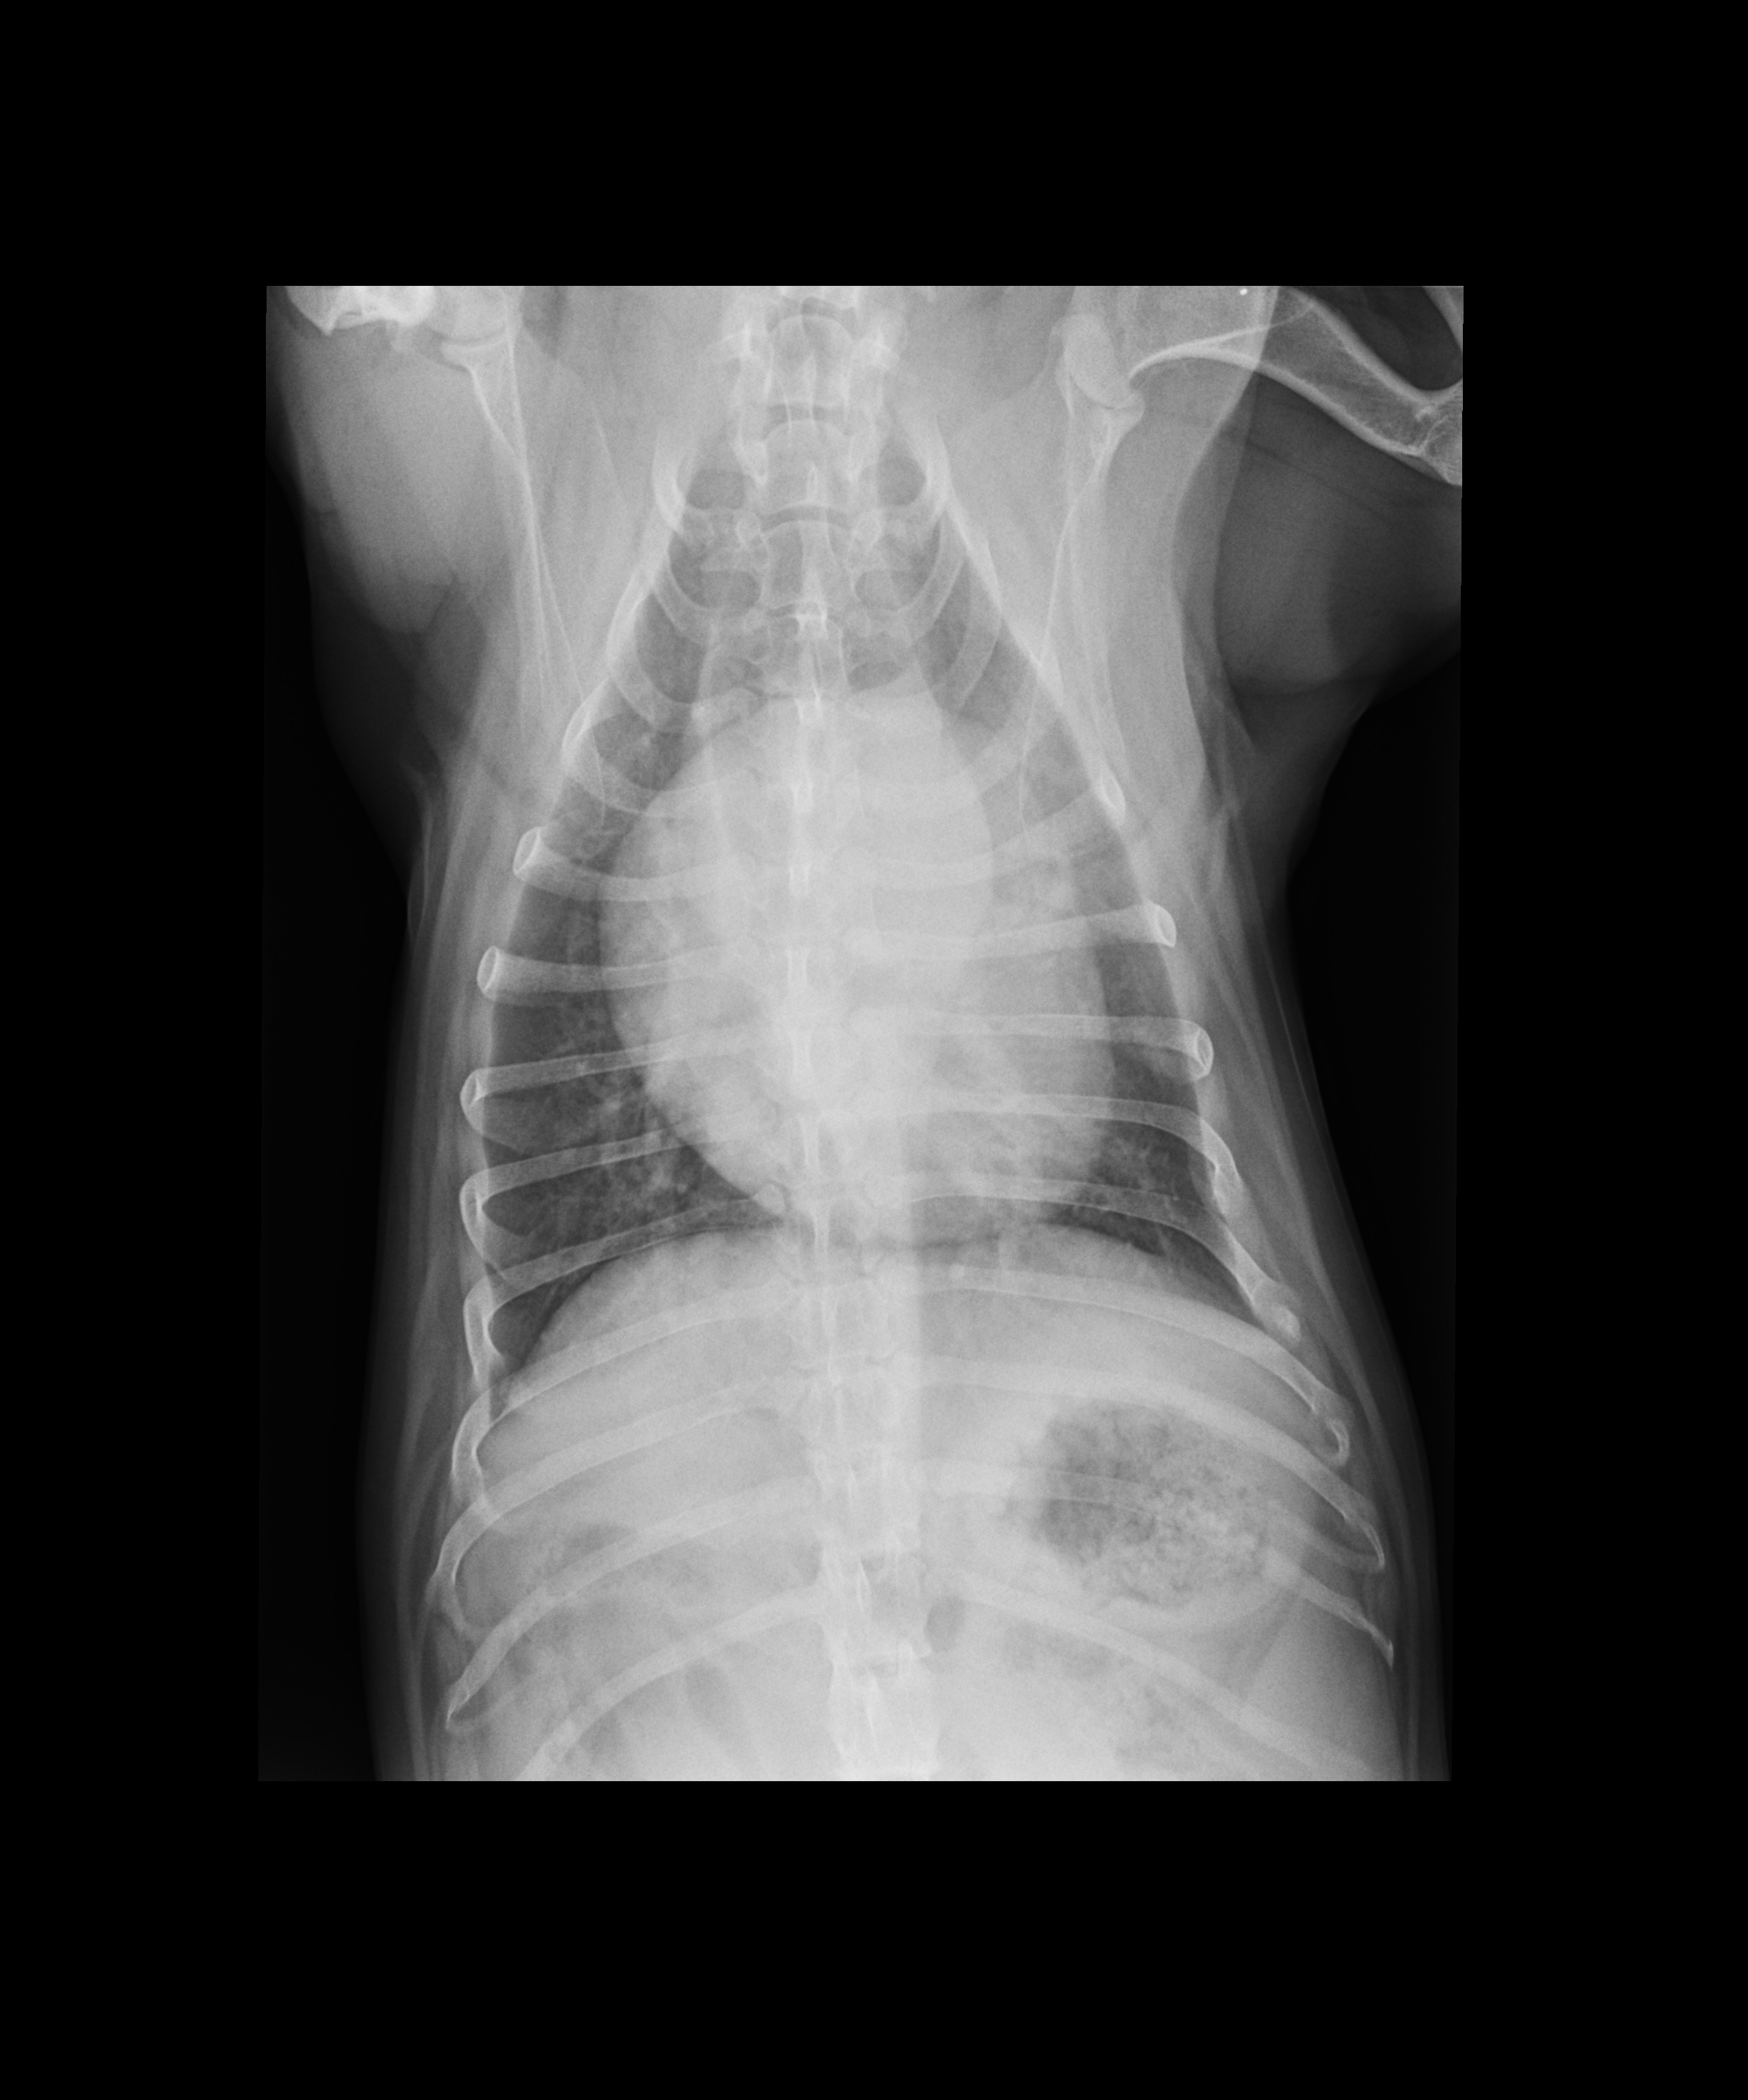

- Connaître les principaux examens à considérer chez un chien présenté en dyspnée aigue

- Connaître les limites de l’examen échographique pour l’exploration d’une dyspnée aigue chez le chien

- Connaître les limites de l’examen sanguin (mesure BNP) pour l’exploration d’une dyspnée aigue chez le chien